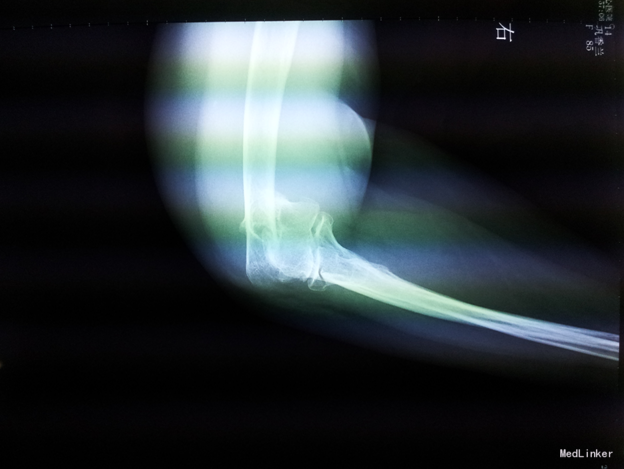

主诉:右肘关节疼痛活动受限5小时。现病史:5小时前,在家中摔倒,意识清醒,先后右膝、左上肢着地,自觉右上肢疼痛,伴活动受限。后就诊于铁西区中心医院,行右肘关节正侧位DR提示肱骨骨折,左膝关节正侧位提示未见异常,未予治疗,现为求进一步诊治来我院就诊

辅助检查:右上肢及手部肿胀,前臂绷带悬吊中,右肘关节及周围压痛,可触及骨擦音,骨擦感。左膝关节处肿胀。四肢感觉正常,肌张力正常。右侧握力、右腕背伸4级,余四肢肌力正常。右桡动脉搏动良好。

诊断:右肱骨骨折 治疗:切开复位内固定术